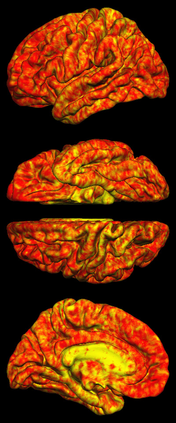

Due to various physical degradation factors and limited counts received, PET image quality needs further improvements. The denoising diffusion probabilistic models (DDPM) are distribution learning-based models, which try to transform a normal distribution into a specific data distribution based on iterative refinements. In this work, we proposed and evaluated different DDPM-based methods for PET image denoising. Under the DDPM framework, one way to perform PET image denoising is to provide the PET image and/or the prior image as the network input. Another way is to supply the prior image as the input with the PET image included in the refinement steps, which can fit for scenarios of different noise levels. 120 18F-FDG datasets and 140 18F-MK-6240 datasets were utilized to evaluate the proposed DDPM-based methods. Quantification show that the DDPM-based frameworks with PET information included can generate better results than the nonlocal mean and Unet-based denoising methods. Adding additional MR prior in the model can help achieve better performance and further reduce the uncertainty during image denoising. Solely relying on MR prior while ignoring the PET information can result in large bias. Regional and surface quantification shows that employing MR prior as the network input while embedding PET image as a data-consistency constraint during inference can achieve the best performance. In summary, DDPM-based PET image denoising is a flexible framework, which can efficiently utilize prior information and achieve better performance than the nonlocal mean and Unet-based denoising methods.